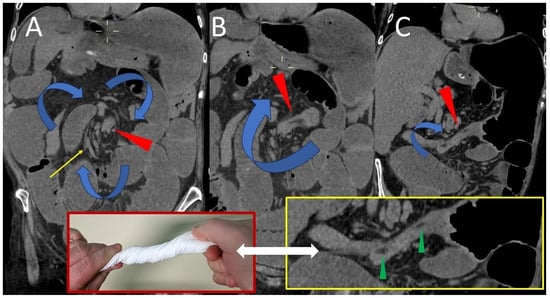

A radial torsion of the ascending colon with terminal ileum resulted in a closed-loop pattern blockage of the caecum, as revealed by abdominal CT imaging. The cecum, markedly distended with air, appeared inverted and occupied the upper left quadrant of the abdomen, exhibiting a morphology reminiscent of a 7–8-week-old fetus, complete with a cord-like structure (Figure 1).

Figure 1. Coronal (A) CT scan shows the cecal volvulus, loop type; the caecum, greatly distended with air (green arrowhead), was inverted and filled the upper left region of the abdomen. Three-dimensional volume rendered (B) image of computed tomography, simulates a double-contrast barium study, demonstrated the cecal volvulus (green arrowhead), ileocecal valve and terminal ileum (yellow arrowhead).